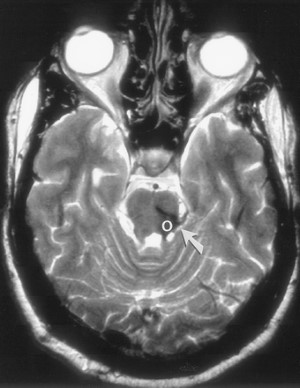

Thoái hoá phì đại nhân trám (hypertrophic olivary degeneration, HOD) được xem là sự thoái hóa xuyên khớp thần kinh (transsynapse) xảy ra sau tổn thương ở tam giác Guillain và Molaret (Hình 8), như là chảy máu trần cầu não (tegmentum pontis) hoặc chảy máu nhân răng. Thoái hoá phì đại nhân trám được thấy ở phía cùng bên với chảy máu trần cầu não và ở bên đối diện với chảy máu nhân răng. Các vùng cường độ tín hiệu cao trên ảnh T2-W xuất hiện sau cơn đột quỵ 3 tuần, và tồn tại dài đến 8 năm sau. Phì đại của các nhân trám dưới nhìn thấy 5-15 tháng sau cơn đột quỵ. Các bất thường nhân trám hai bên có thể thấy khi chảy máu trần cầu não liên quan đến cuống tiểu não trên (Hình 9). Các thay đổi bệnh lý chính của HOD bao gồm thoái hóa hốc của các neuron to lên, phì đại các tế bào hình sao, và tăng sinh tế bào thần kinh đệm (gliosis). Các vùng cường độ tín hiệu cao ở các nhân trám dưới là do thành phần nước tăng lên và tăng sinh các tế bào thần kinh đệm [17].

Hình 9. Chụp MRI 29 tháng sau xuất huyết cầu não. Ảnh T2W fast spin-echo (TR/TE = 6000/92), echo train length = 12) ở mức nhân trám dưới cho thấy phì đại và tăng tín hiệu ở cả hai nhân trám. (AJNR 2000 21: 1073-1077)